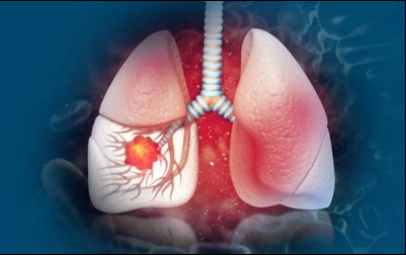

6. 폐암 초기 증상 - 혈담

혈전은 반드시 폐암이 아니어도 나타날 수 있습니다 . 혈담이란 기침 후에 피가 나오 거나 가래에 피가 섞여 있는 것을 혈담 이라고 합니다 . 그러나, 의심스러운 폐암의 초기 증상의 혈담은, 선홍색의 비교적 선명한 피가 나오는 것을 의심해 봐야 합니다 . 이것은 암세포 때문에 폐가 괴사하기 때문 입니다 . 이 경우 폐암 초기보다는 암세포가 확장되었다고 보는 것이 좋습니다 . 폐암 환자의 25% 가 혈담을 했다고 통계가 나온 적이 있습니다 .